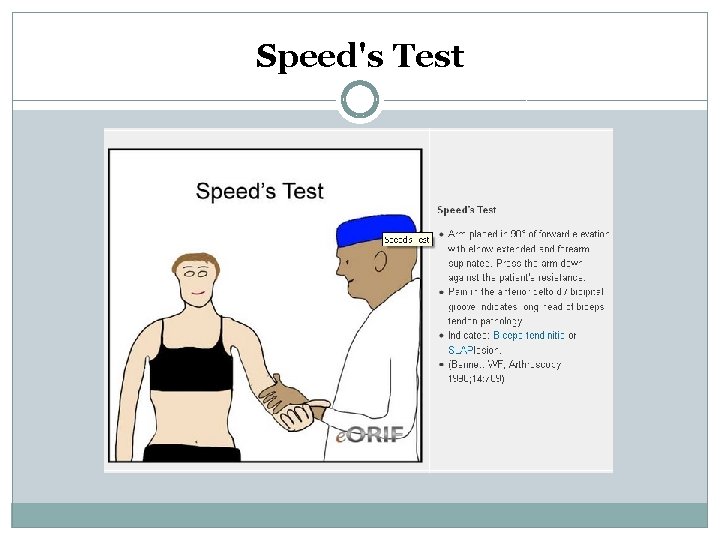

Speed's Test